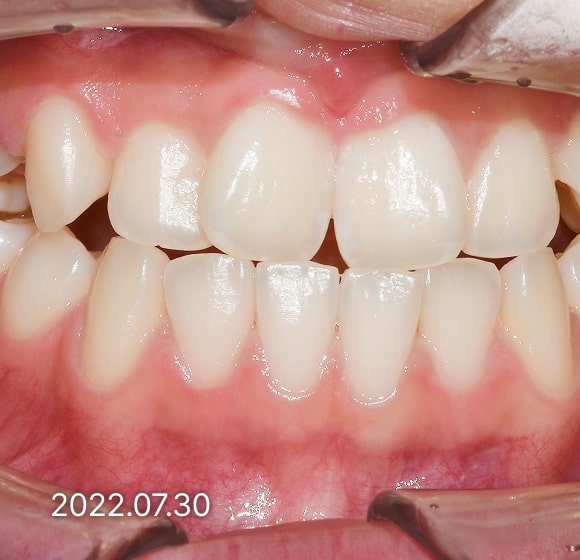

BEFORE / AFTER

전후 변화로 보는 치료사례

본 사진은 진심을담은치과교정과 치과의원에서

치료한 환자의 동일 인물 전·후 사진입니다.

개인의 구강 상태 및 관리 방법에 따라 통증 및 잇몸 염증,

턱관절 불편감 등의 부작용이 발생할 수 있습니다.

치료 전 치료 후

덧니, 삐뚤한 치열